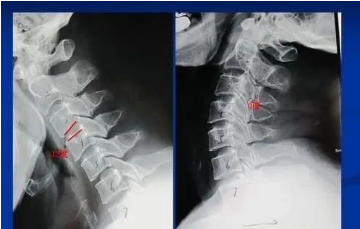

低头时颈椎曲度变直